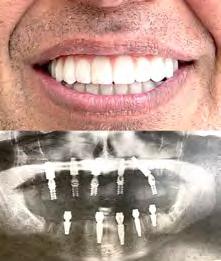

Лучшее качество услуг и материалов по разумной цене! Консультация и 3D снимок в подарок.

Установка одного импланта от

Одна из недавних операций:

Все-на-5-ти имплантах + несъемные зубы за 1 день

Высококлассные услуги по Зубной Имплантации в современной клинике, лимиторованной на установку имплантов.

* - установка 1 (одного) импланта не включая абатмент и коронку. Имплантация будет производится одним из специалистов клиники под руководством доктора Александра Антипова, челюстно-лицевого хирурга. Цена указана для пациентов, оплачивающих наличными.

(916) 827-3605